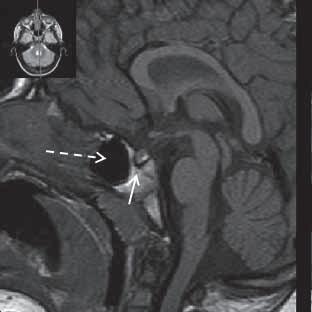

Chiari I: CT a MR zobrazí malou zadní jámu lební, absenci cisteren zadní jámy lební, pokles tonzil, krátký a konkávní klivus, poruchu cirkulace mozkomíšního moku v oblasti foramen magnum a následný hydrocefalus. MR navíc může prokázat edém krční míchy a ve vysokém procentu případů hydrosyringomyelii.

Chiari II: CT a MR zobrazí malou zadní jámu lební, absenci nebo výraznou redukci cisterny cerebelomedulární a dalších kmenových cisteren, konkávní klivus. Mohou být abnormality v oblasti foramen okcipitale magnum, nízký úpon tentoria, někdy absence nebo fenestrace falx cerebri. MR lépe ukáže kaudálně uloženou a protáhlou IV. komoru (někdy je přirovnávána až ke stéblu slámy), protažený pons a další možné, přidružené abnormality (hydrosyringomyelii, agenezi, hypogenezi nebo fenestraci corpus callosum…).

Obr. I.1.7a Sestup mozečkových tonzil (šipka), Chiariho malformace I

Obr. I.1.7b Sestup mozečkových tonzil, „pek like“ (šipka), Chiariho malformace I c d

Sestup mozečkových tonzil,

Myelomeningokéla